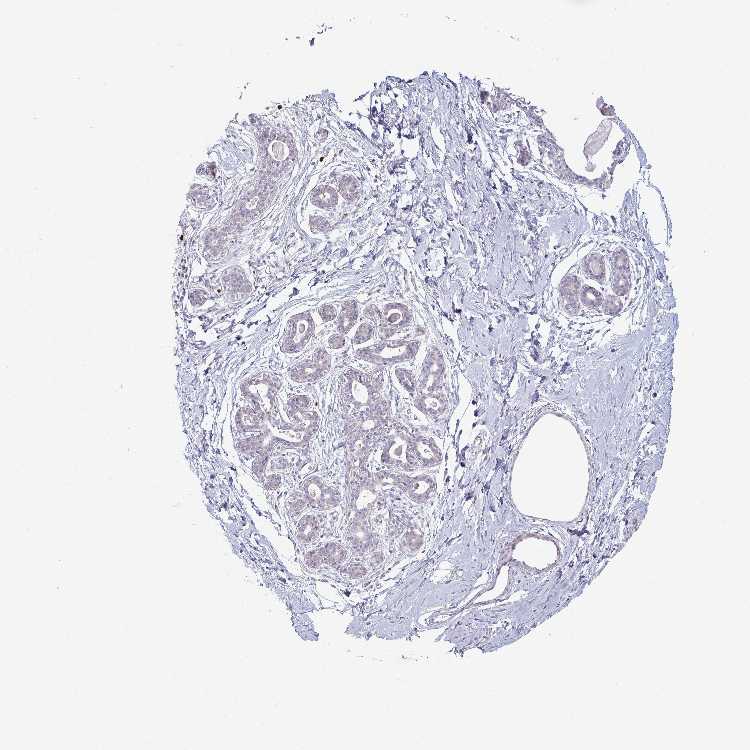

BREAST - Antibody stainingi

Antibody staining in the annotated cell types in the current human tissue is reported as not detected, low, medium, or high, based on conventional immunohistochemistry profiling in selected tissues. This score is based on the combination of the staining intensity and fraction of stained cells.

Each image is clickable and will lead to virtual microscopy that enables deeper exploration of all samples and also displays staining intensity scores, fraction scores and subcellular localization as well as patient and tissue information for each sample.

Antibody HPA059737

Adipocytes Not detected

Glandular cells Not detected

Myoepithelial cells Not detected